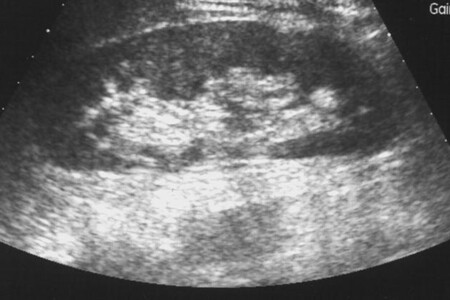

Diagnostika pneumotoraxu vychází ze zjištěných příznaků, tedy zrychlené tepové frekvence a poklesu tlaku. Dále lékař zjišťuje snížené či zcela vymizelé dýchání na postižené straně. K ověření diagnózy se užívá rentgenu hrudníku, kde můžeme vidět výrazně zvětšenou pohrudniční dutinu, na postižené straně malou stlačenou plíci a odtlačené srdce směrem ke zdravé straně.